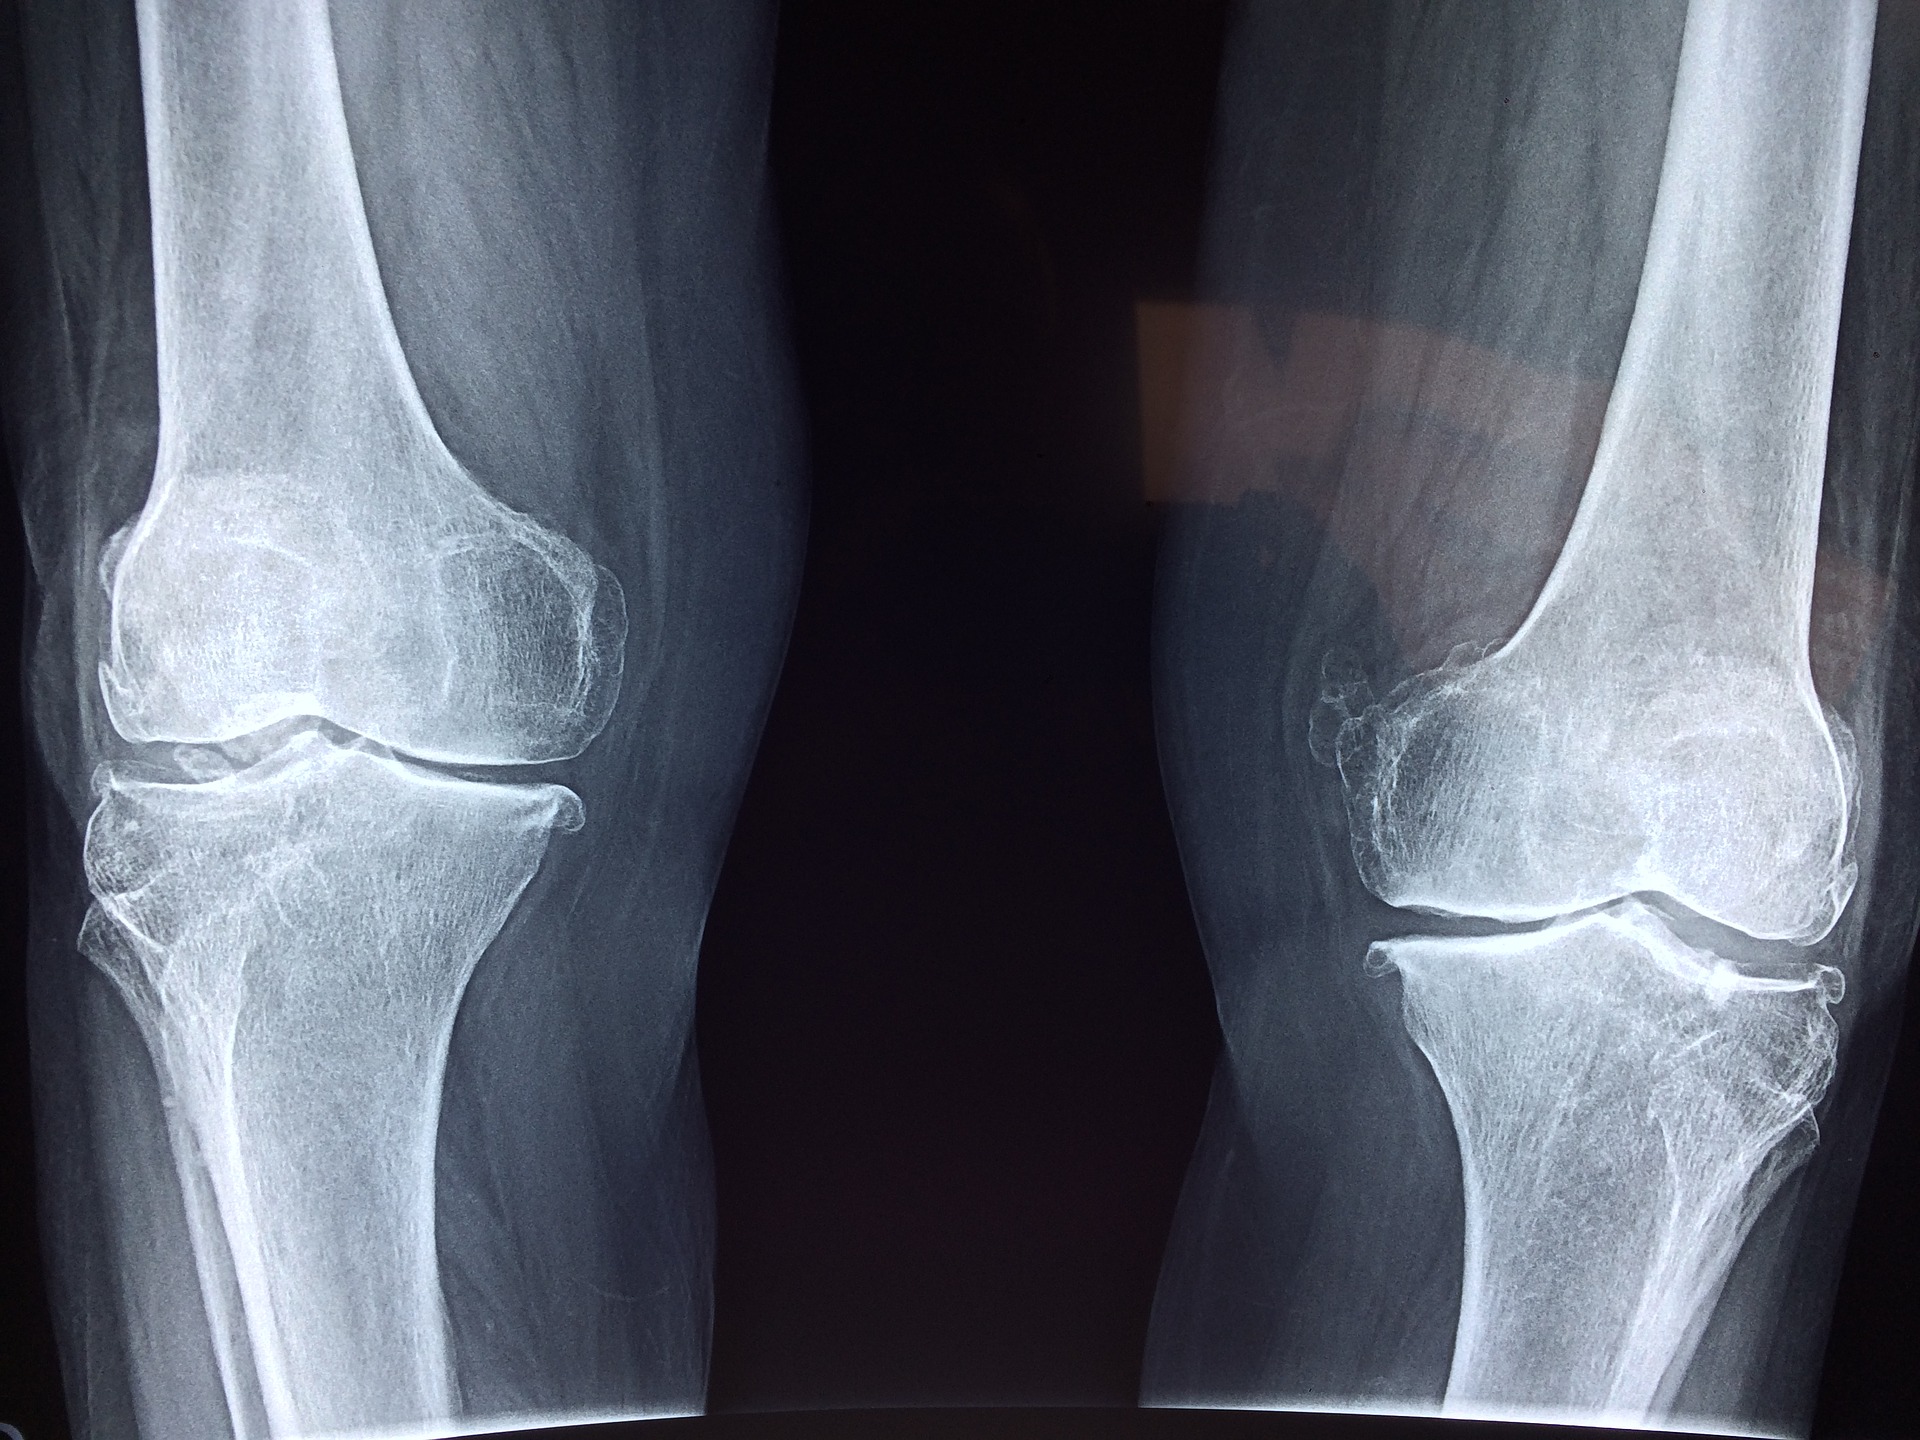

Knee Osteoarthritis

Knee osteoarthritis (OA) is a condition where the cartilage between the ends of the bones that make up the knee wear down causing the classic symptoms of morning stiffness and pain. Many people also experience a cracking or crunching feeling during normal range of motion of the joint.